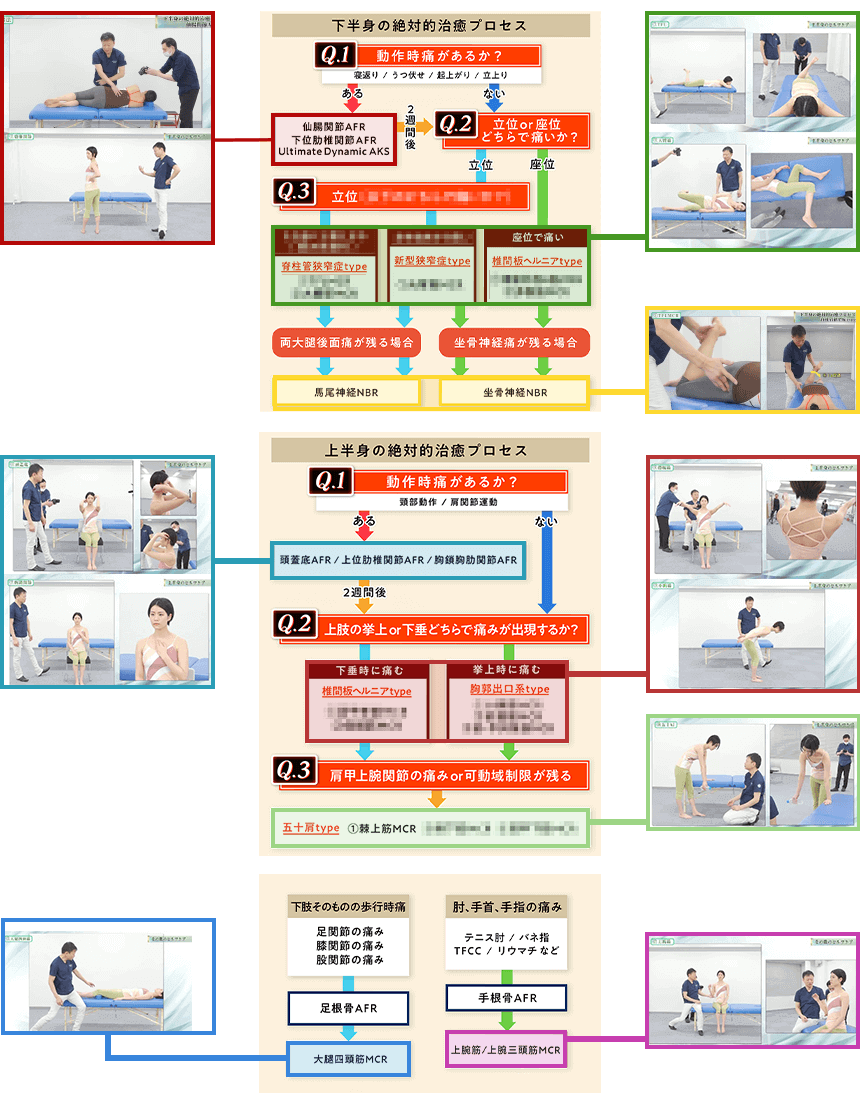

これが、AKS療法®の絶対的治癒プロセスです。この図は患者さんが来た時の問診時に使えるフローチャートになっており、あなたは上半身、下半身それぞれに対応する3つの質問「Final 3 Qestion」を患者さんに聞き、絶対的治癒プロセスに則ってチャートを進むだけで、原因が明確になり、アプローチする手技が明確になるのです。

- ①フローチャートに沿って誰でも出来る3つの質問をする

⇒医師も分からない真の症状の原因が浮き彫りに! - ②チャートから導き出された手技をやるだけ

この絶対的治癒プロセスを使えば、たとえあなたが解剖学をまったく知らない素人だとしても、患者さんの痛みの真の原因が分かるようになるので、原因が分からずに全身を揉んでみたり、治療に悩んだり不安になることがなくなるのです。

つまり、この絶対的治癒プロセスはゴッドハンドと同じ診立てや問診、治療計画を立てるためのカンニングペーパーのようなものであり、手技の使い方をナビゲートしてくれるものです。

この、たった3つの質問で症状の根本原因を明らかにし、患者さんの未来予測までできるようになる絶対的治癒プロセスと手術宣告された重症患者さんでも回復に導く手技の両方が揃っている最強の治療法が「AKS療法®-Final-」であり、“素人でも重症患者さんを回復に導ける”と自信を持っておススメできるのです。